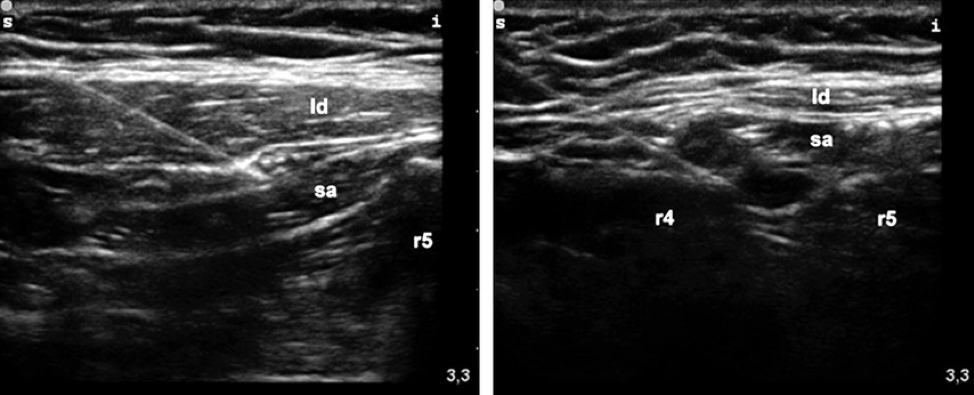

While there is limited evidence, some recommend targeting the fascial plane just deep to the serratus anterior may improve the analgesic effect for posterior rib fractures [7]. Comparison of the anterior and posterior approach can be seen in Figure 6. Remove the needle and place a dressing on the puncture site. Continue to monitor the patient after completion of the procedure to determine whether the block was effective and to identify any complications.

Figure 6: Comparison of needle tip placement for anterior (left) versus posterior (right) serratus anterior plane block. Ld = latissimus dorsi, sa = serratus anterior, r4 = rib 4, r5= rib 5. [11]